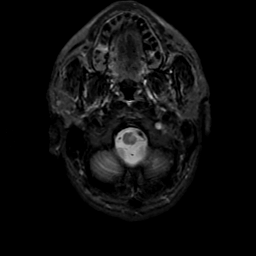

MR Study #22, December 1, 1991 -- Slice #3

[Home][Help][Clinical][Tour 1][Tour 2] Slice 3